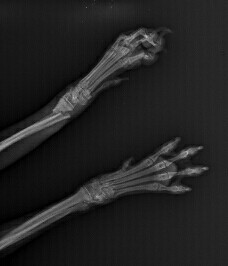

• 흉, 복부 방사선 검사 방사선 검사는 골격계의 이상을 진단하는 기초검사입니다. 방사선 검사를 통해 골격계의 선천적 이상 등을 진단하게 됩니다. 흉부 방사선 사진을 통해 기관의 이상 유무 판결, 심장 크기 및 위치의 변화 등을 진단하게 됩니다. 복부 방사선을 통해 방광의 결석, 복강 실질장기의 크기 및 위치 변화 등을 진단할 수 있습니다. 또한, 드물게 발생하는 선천적 결손증의 일부를 진단하게 됩니다.

• 흉, 복부 방사선 검사 노령기의 질환 중 상당수가 종양성 질병과 관련이 있습니다. 정기적인 방사선 검사를 통해 종양성 질환의 발병 유무 및 전이여부를 평가합니다. 심장의 외형변화, 폐 실질의 이상 변화 등을 검사하고 지속적으로 관리하여야 합니다. 체표의 종양성 질환은 눈으로 관찰이 가능하지만 심부의 종양은 관찰이 어렵습니다. 심부의 종양성 변화를 비교적 쉽게 관찰할 수 있는 검사법이 방사선검사입니다. 노령기는 약 6개월단위 정기 검사가 필요합니다.